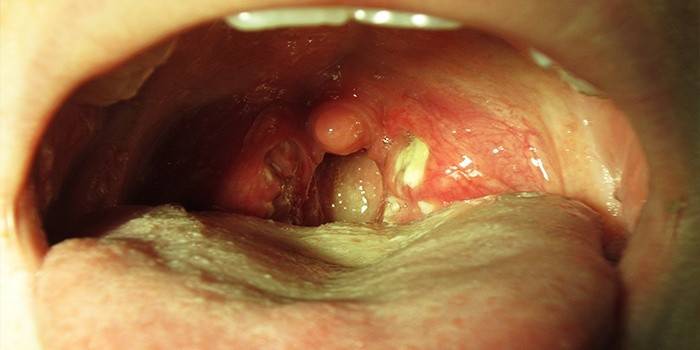

· скупчення білувато-жовтого нальоту на слизових оболонок гортані, дужках і язичку (легко видаляється);

· освіта гною на мигдалинах;

· гіперемія слизових оболонок мигдалин і горла;

На мигдалинах з’являється жовто-білий гнійний наліт, сильна біль в горлі іррадіює в скроню або вухо. Стафілокок в носоглотці викликає нежить і набряк слизової оболонки.

- Почервоніння глотки, мигдаликів. При наявності золотистого стафілокока в горлі помітна виражена набряклість гланд. Біль при ковтанні, через деякий час больові відчуття виникають при вдиху, потім стають постійними.

- Через кілька годин після початку недуги можуть бути помітні білястий наліт або гнійні освіти на мигдалинах.